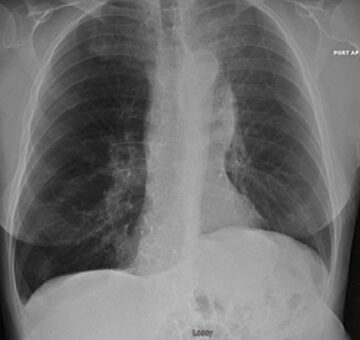

76 y/o male with homogenous emphysema and multiple comorbidities came off oxygen after treatment (Result not typical)

Successful atelectasis of the right middle lobe with 80% fissure completeness score